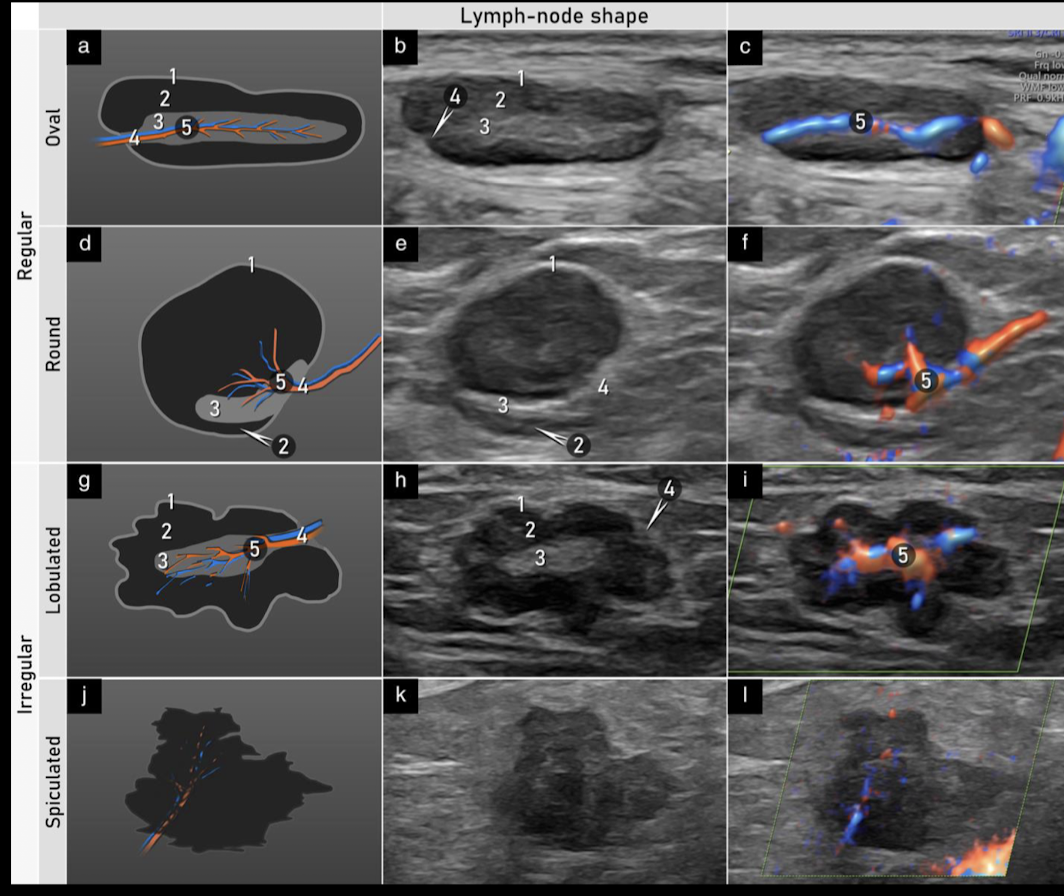

USG

lo mejor, primer recurso

ganglio homogeneo hipoecoico

se preserva forma e hilio hiperecoico: benigno

hipervascularidad

perdida de la morfologia: maligno

Etapas de un nódulo